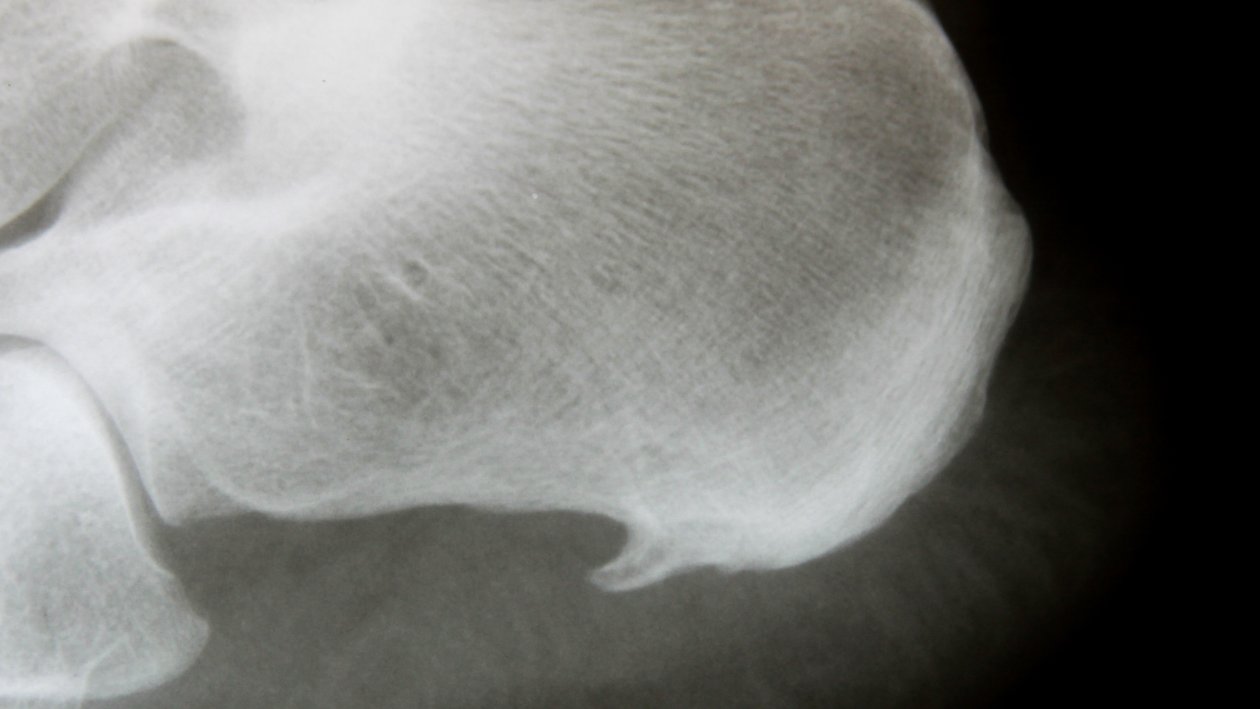

(Aufzeichnung Online-Seminar) Schmerzen beim Laufen, Stehen und Gehen haben meist unterhalb der Ferse im Bereich der Fußsohle ihren Ursprung. Jeder Schritt und auch das einfache Stehen werden bei einem Fersensporn und einer Plantarfasziitis, also dem Schmerz unter der Ferse, zur Qual. Besonders am Morgen, kurz nach dem Aufstehen, leiden Betroffene unter Belastungsschmerzen, die sich bis in die Zehen oder den Unterschenkel ziehen können.

Was können Sie tun, um den typischen Schmerzen des Fersensporns entgegenzuwirken? In diesem Video werden Behandlungsmöglichkeiten von E wie Einlagen bis S wie Stoßwelle thematisiert. Zudem gibt es einige Tipps und Tricks gegen den Schmerz beim Laufen.